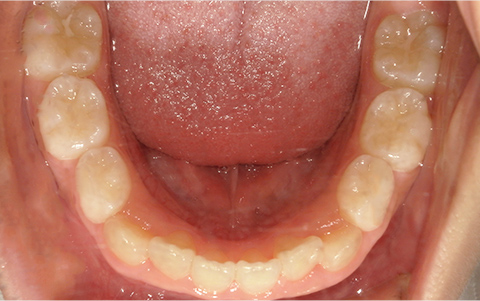

このような歯並びで

お悩みではないですか?

歯並びが悪い

症例